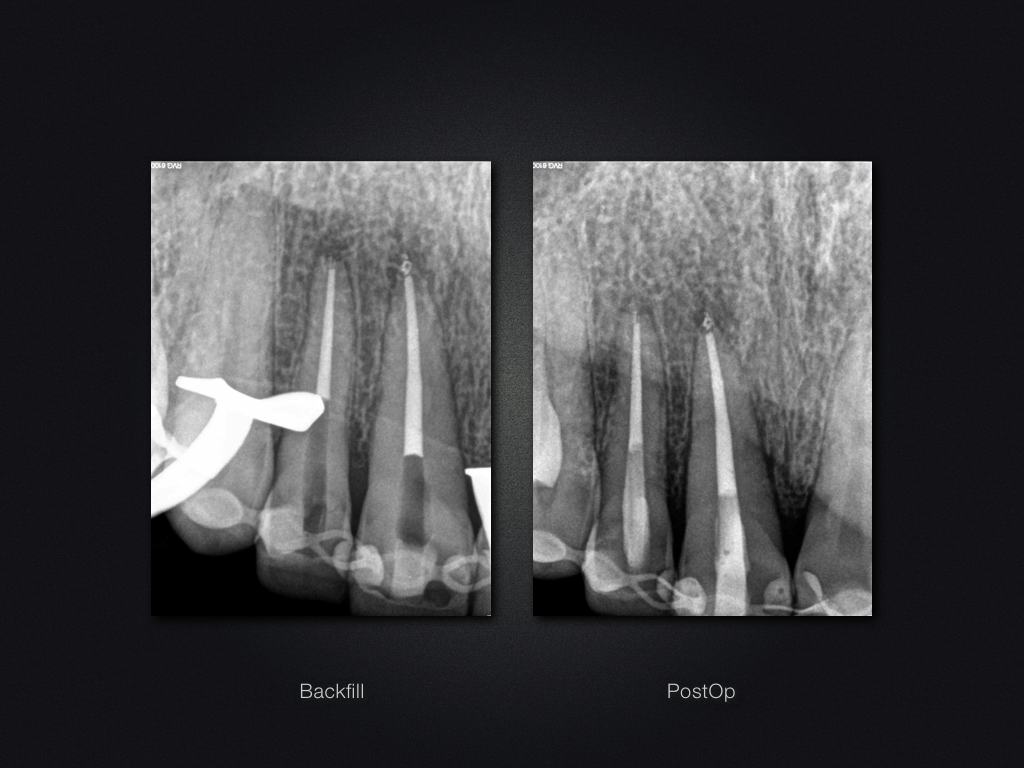

Ansonsten chemo-mechanische Aufbereitung, NaOCl 5%-, 17 % EDTA, ultraschallaktivierte Irrigation nach jeder Feile, Spüllösung erwärmt auf ca. 45 Grad Celsius, Obturation in modifizierter Schilder-Technik.